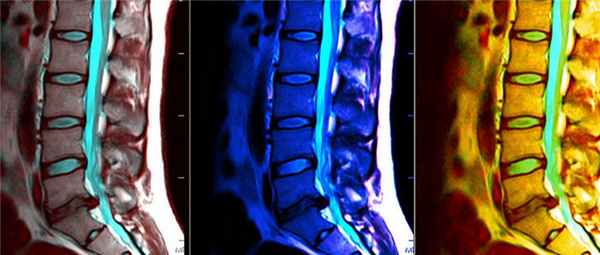

Предоперационная визуализация заключалась в МРТ головного мозга с захватом краниовертебрального перехода и в МРТ спинного мозга по длиннику в зависимости от уровня сирингомиелии. МРТ-исследование проводили на томографах Signa HDxt 1,5T (General Electric, США) с напряженностью магнитного поля не менее 1,5 Тл в аксиальной, сагиттальной и коронарной проекциях, а также в режиме гидрографии для оценки ликвородинамики в области краниовертебрального перехода.

Основными критериями диагностики аномалии Киари служили данные нейровизуализации (рис. 4) [21, 22, 23] и клинического обследования, основанного на выявлении характерных клинических синдромов (мозжечкового, гипертензионно-гидроцефального, сирингомиелического, корешкового, бульбарного и синдрома вертебробазилярной недостаточности [24]). На МРТ при МК I в большинстве случаев определяют опущение миндалин мозжечка ниже линии Мак-Рея, сирингомиелию, компрессию ствола головного мозга. При мальформации Киари II типа (МК II) также определяется опущение миндалин мозжечка, Z-образная деформация продолговатого мозга, четверохолмное сращение (клювовидный изгиб в области четверохолмия), удлинение продолговатого мозга, низкое прикрепление головного мозга. При МК II на МРТ встречается гидроцефалия, сирингомиелия в области краниовертебрального перехода, изолированный IV желудочек, церебелломедуллярная компрессия, агенезия/дисгенезия мозолистого тела [5].